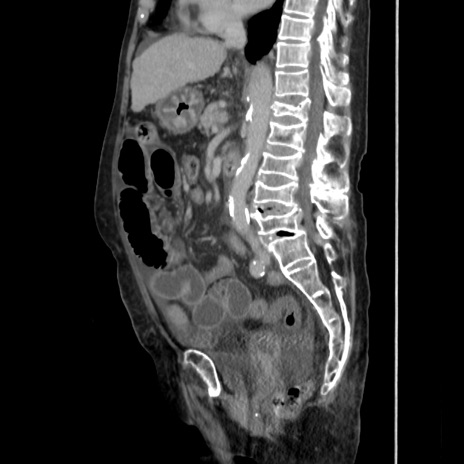

症例31(矢状断像)

【症例】80歳代 女性

【主訴】腹部膨満感

【現病歴】他院にて肝硬変にてフォロー中。1週間前から便秘、腹部膨満感、臍部腫瘤あり受診となる。

【既往歴】肝硬変

【身体所見】腹部膨隆あり、皮膚変化なし、疼痛なし。

【データ】WBC 4600、CRP 0.25